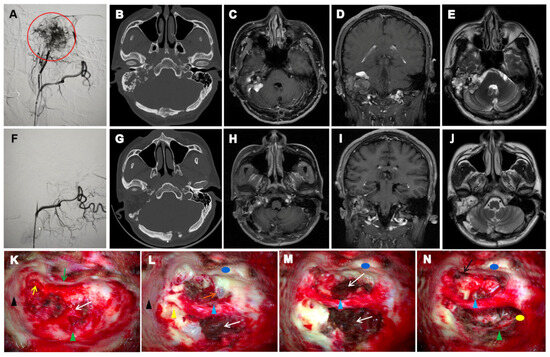

| HRCT | Assess bony erosion, tumor boundaries, and preoperative planning | ipsilateral temporal bone “moth-eaten” or honeycomb-like osteolytic destruction with crest-like/granular calcifications and residual bone formation | CT localization typically revealed tumour centres in the vestibular aqueduct operculum region, with early-stage lesions showing periaqueductal osteolysis and preserved surrounding architecture that facilitated origin identification. In advanced cases, the jugular foramen or subdural extension often obscured primary site determination. |

| MRI | Early screening, Lesion localization and classification, tumor relationship with the inner ear, brainstem, and cranial nerves, postoperative follow-up and long-term surveillance | hyperintense peripheral tumour margins and flow voids on T1-weighted imaging; and heterogeneous signal intensity on T2-weighted imaging. | Superior soft tissue contrast allows early detection of subclinical lesions, precise delineation of tumor extent, and assessment of involvement of critical neurovascular structures. Essential for surgical planning and long-term surveillance, especially in bilateral or recurrent VHL-associated cases. |

| DSA | Assess vascular supply and guide preoperative embolization | Tumor blush from external carotid artery branches; occasionally supplied by internal carotid or vertebral artery branches | Defines feeding arteries; essential for embolization planning and minimizing intraoperative bleeding risk |